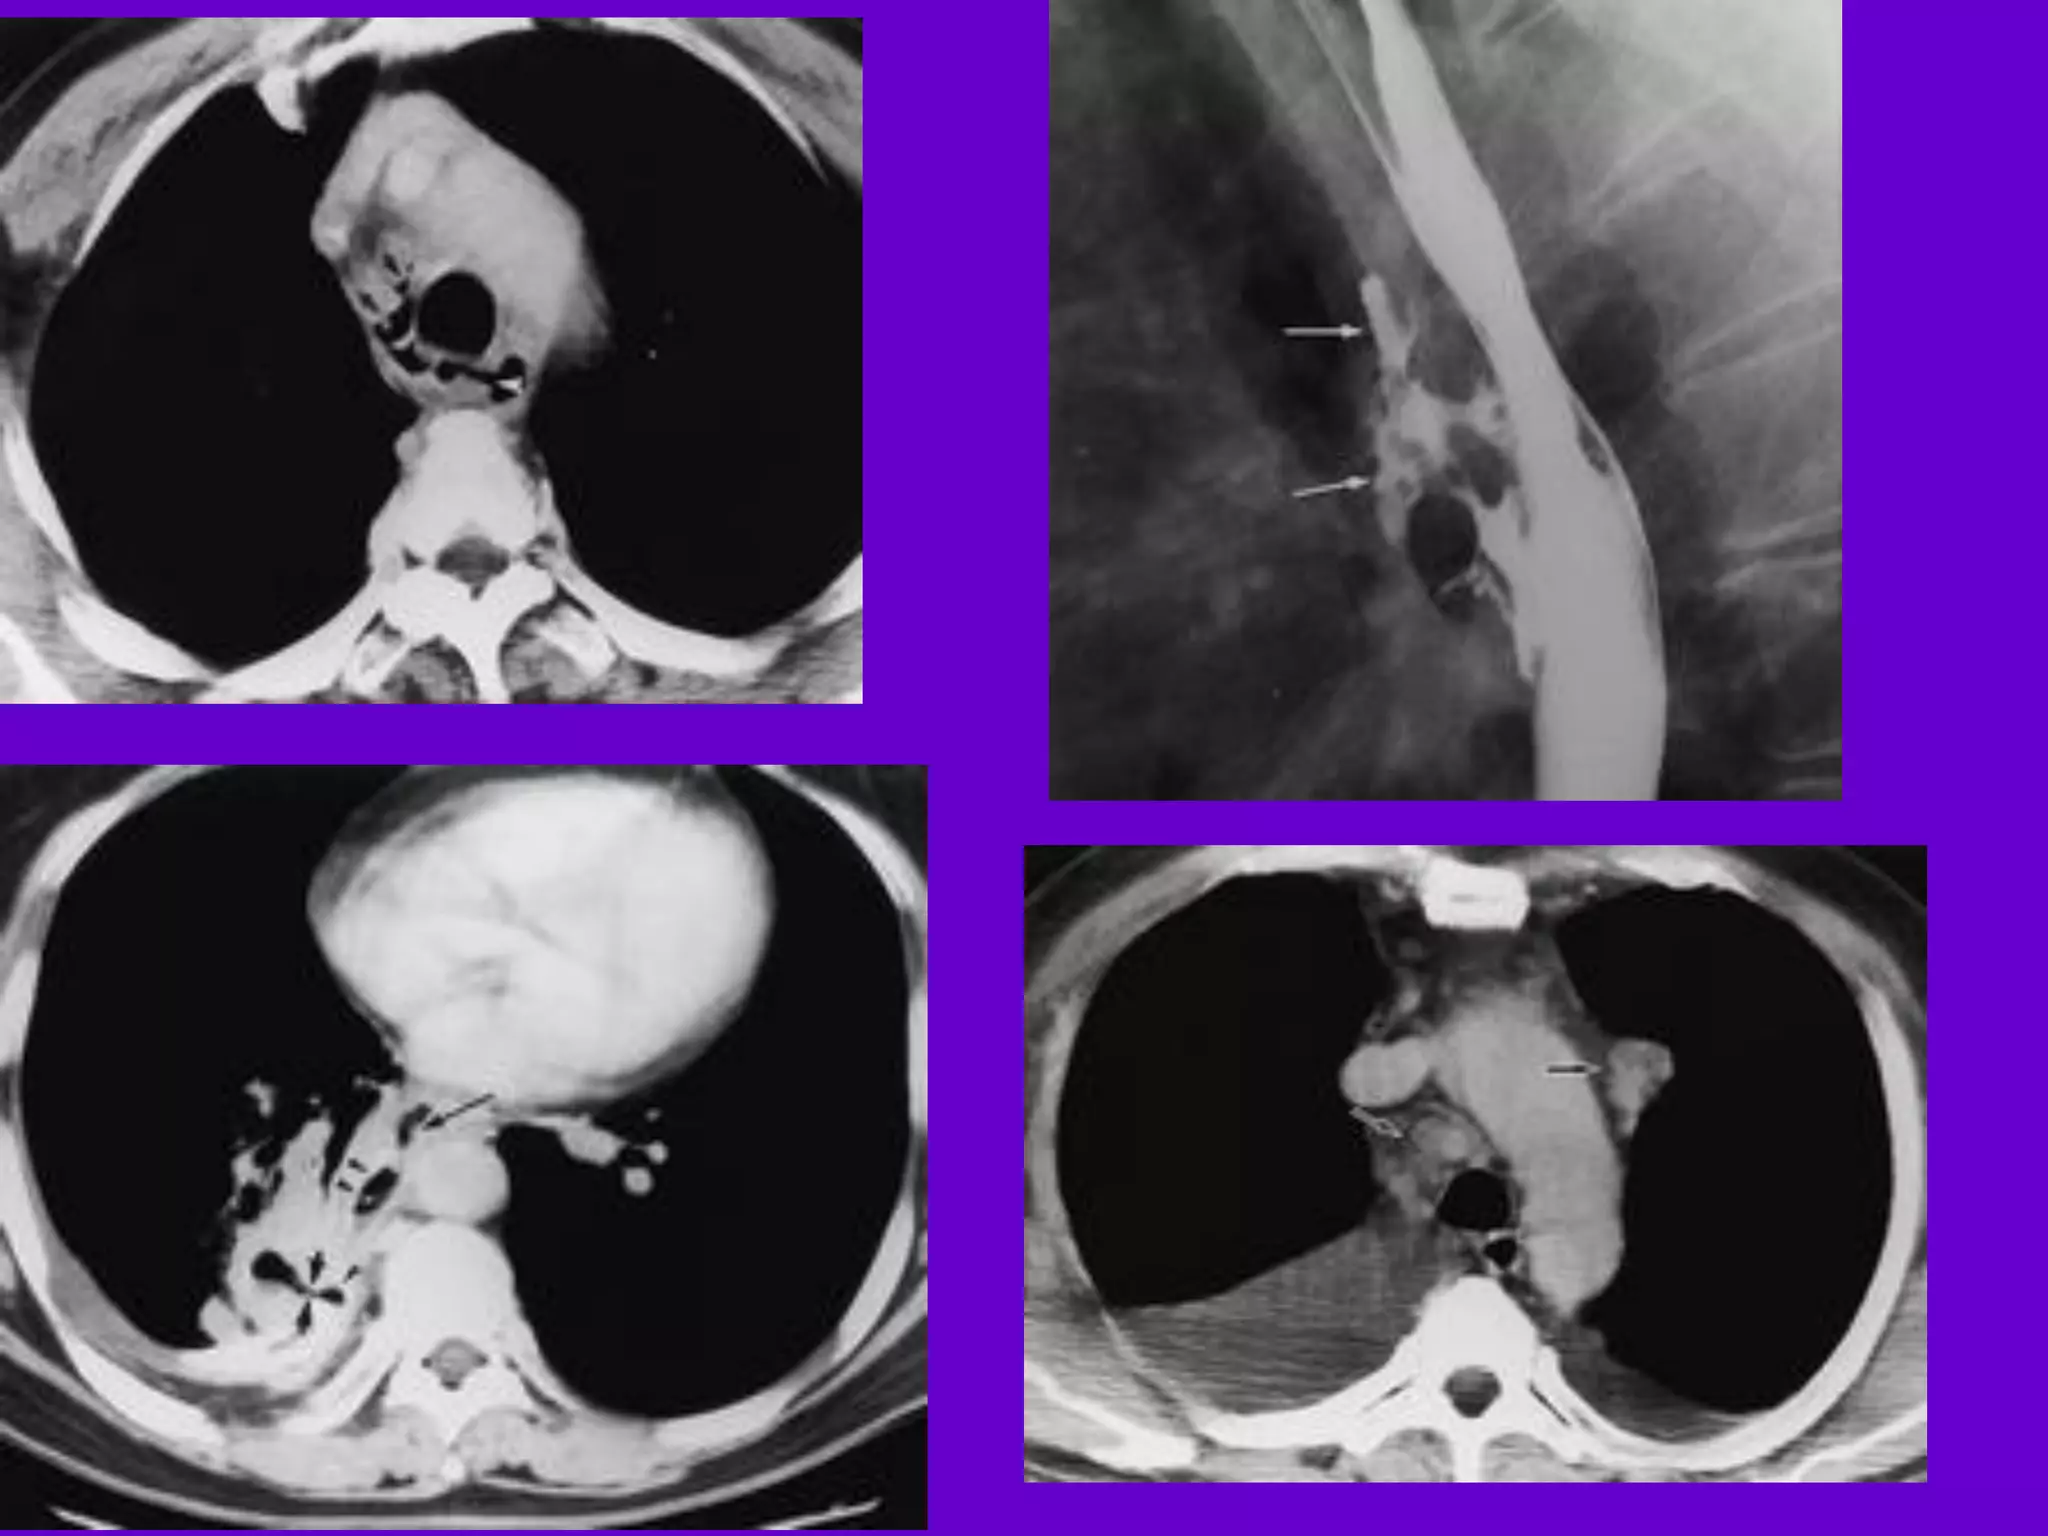

CT Scan andMRI Scan in the diagnosis of TB 􀂄 The advent of CT and MRI imaging in the last two decades has redefined the approach in analysis of various diseases including TB.* 􀂄 CT and MRI have shown several advantages over conventional radiology in early diagnosis and follow-up of TB in different parts of the body. *Buxi TBS Indian J Pediatr 2002;69:965-972

Pulmonary TB : LobarPneumonia 􀂄 CT is superior than plain CXR in picking up the consolidation, atelectasis and the hilar LN thereby making the diagnosis easy. 􀂄 MRI reveals some of these changes, however, CT is the diagnostic modality of choice in such cases. 􀂄 Bronchopneumonia 􀂄 On CT it is usually B/L and widespread, not always symmetrical involvement of lungs. 􀂄

Hilar and Mediastinal Lymphadenopathy CTand MRI depict the hilar and mediastinal LN equally well. 􀂄 Calcification in the nodes is however better seen on CT. 􀂄 Necrosis is seen as focal areas of low attenuation on a CECT. 􀂄 On MRI focal necrosis is seen as areas of increased signal intensity on T2W images. 􀂄 EBTB 􀂄 HRCT is sensitive in the detection of early endobronchial spread of disease. 􀂄

Miliary TB 􀂄 Earliestform of miliary TB is detectable on HRCT. 􀂄 Coalescing nodules result into patchy irregular opacities and HRCT shows this variation effectively and has been described as “snowstorm appearance”. 􀂄 HRCT shows cavitation, which is not evident on plain CXR. Pleural Effusion 􀂄 􀂄 CT is sensitive to diagnose and define even minimal pleural effusion/pleural calcification. 􀂄 Pleural fluid is seen on inversion recovery MR images as areas of increased signal intensity along the inner aspects of the chest wall.